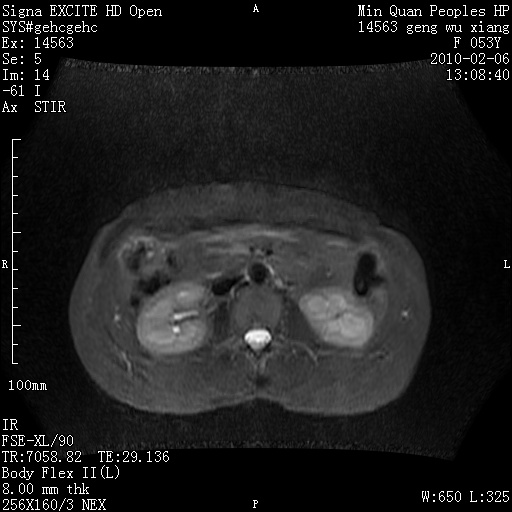

标题: MRI2762:胆道梗阻原因?

f,53y,全身黄染多日。

高位胆道梗阻 胆管癌可能性大

支持 高位胆道梗阻 胆管癌可能性大。